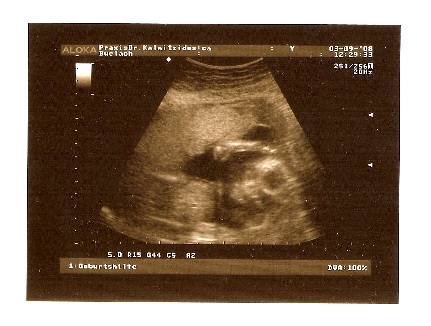

Der kleine Untermieter/die kleine Untermieterin ist nun schon 20cm gross (20. Schwangerschaftswoche)

Der kleine Untermieter/die kleine Untermieterin ist nun schon 20cm gross (20. Schwangerschaftswoche)